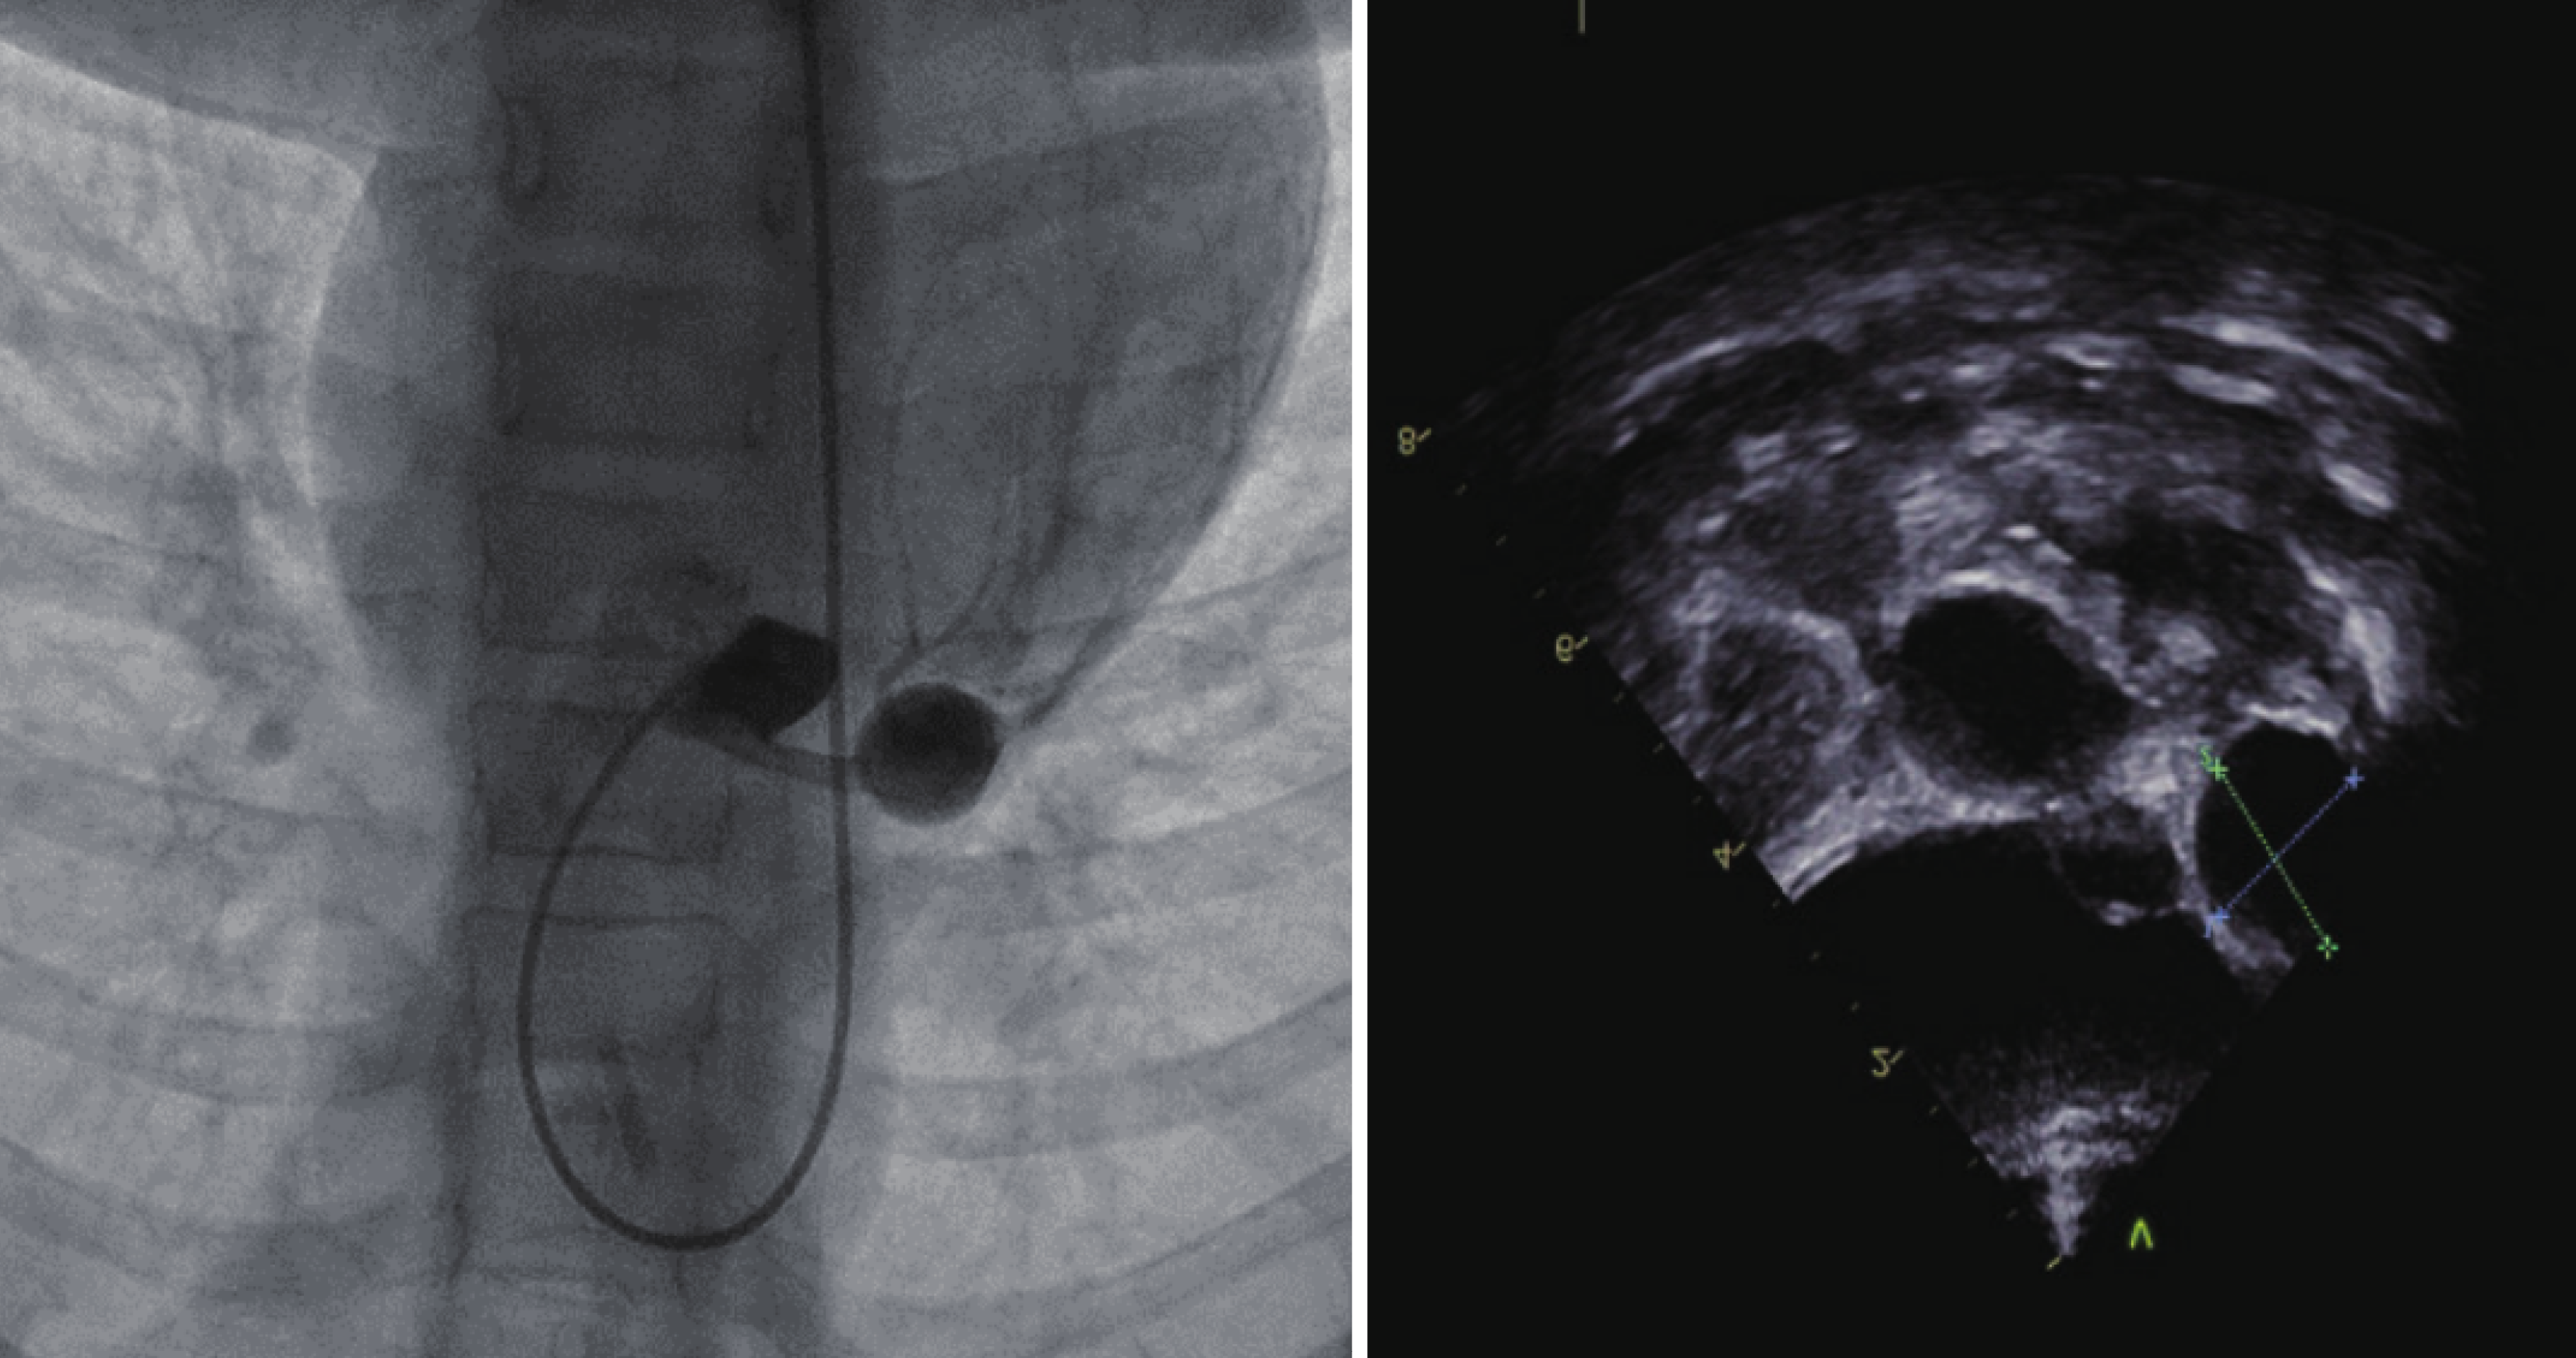

Figure 1 Coronary artery aneurysm and corresponding echocardiography of a coronary aneurysm in a patient with Kawasaki disease (adapted from Zhang et al[7], 2023).

Citation: Zhang M, Cui Q, Zhu DQ, Zhang YQ, Zhong YM, Shen J. [Follow-up Analysis of Coronary Angiography in 21 Children with Kawasaki Disease Complicated by Coronary Artery Lesions]. Shanghai Jiao Tong Daxue Xuebao (Yixueban) 2023; 43: 1535-1541. Published by Shanghai Jiao Tong University (https://xuebao.shsmu.edu.cn/CN/column/column8.shtml).